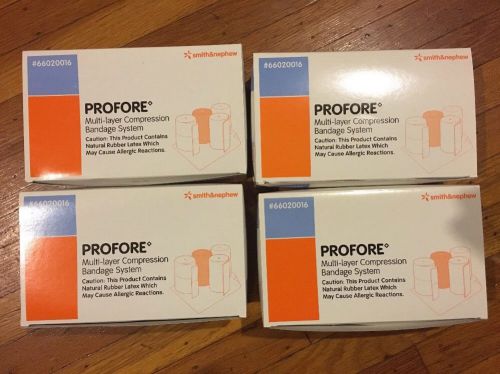

Lot Of 4 Smith & Nephew Profore Multi-Layer Compression Bandage System Four Part